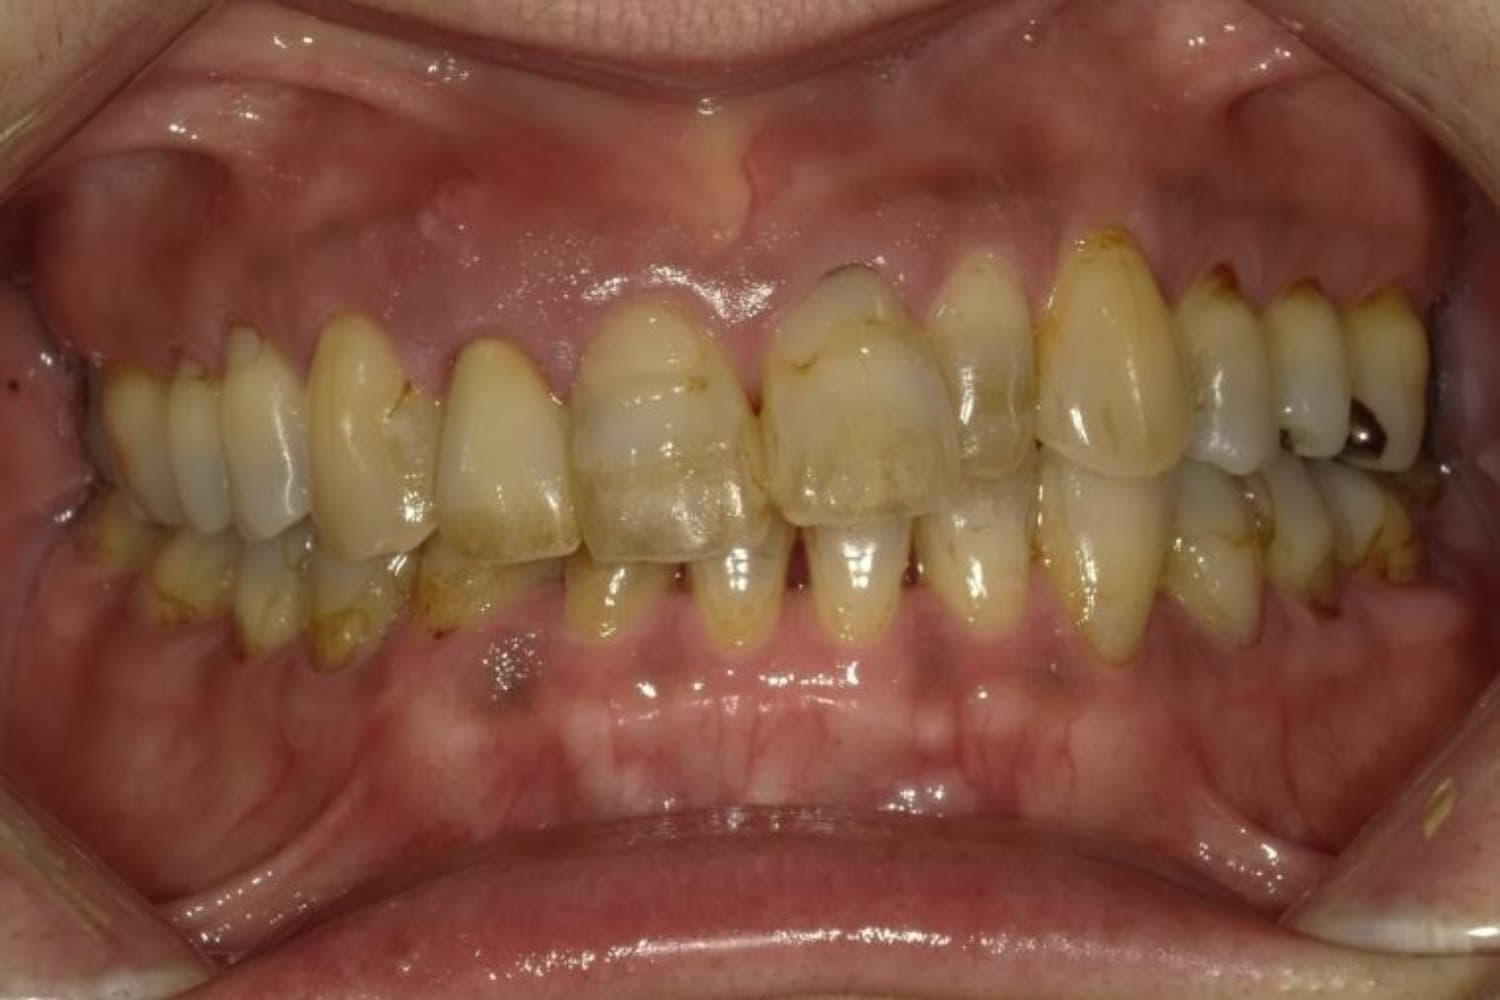

ガタガタとした歯並びや八重歯(1)

Before

After

ガタガタとした歯並びや八重歯をマウスピース矯正(インビザライン)にて治療

主訴

下の前歯のガタガタが気になる

治療期間

2年5カ月

費用

90万円

副作用・リスク

・矯正治療による歯の動きには個人差があり、想定より治療期間が延びることがあります。 ・矯正治療で歯を動かす際に痛みをともなうことがあります。 ・指示された通りに保定装置を装着しないと、歯並びや噛み合わせの後戻りを引き起こす可能性があります。